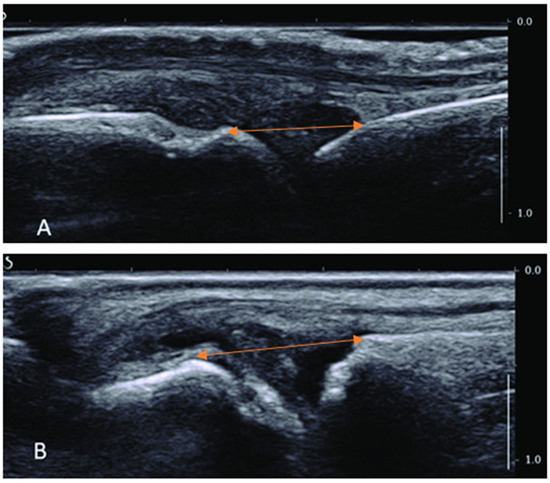

| Mean in mm | N | Std. Deviation | Std. Error Mean | ||

|---|---|---|---|---|---|

| MCP II audible sound group | Pre-distance | 7.99 | 14 | 1.70 | 0.45 |

| Post-distance | 9.70 | 14 | 1.99 | 0.53 | |

| MCP II non-audible sound group | Pre-distance | 7.91 | 11 | 1.84 | 0.55 |

| Post-distance | 8.06 | 11 | 1.77 | 0.53 | |

| MTP II audible sound group | Pre-distance | 5.26 | 12 | 1.05 | 0.31 |

| Post-distance | 6.46 | 12 | 1.30 | 0.39 | |

| MTP II non-audible sound group | Pre-distance | 5.90 | 13 | 1.74 | 0.48 |

| Post-distance | 6.16 | 13 | 1.83 | 0.50 |

| Mean Difference After Manipulation | Std. Deviation | Std. Error Mean | 95% Confidence Interval of the Difference | t | Sig. (2-Tailed) | ||

|---|---|---|---|---|---|---|---|

| Lower | Upper | ||||||

| MCP II audible sound group | 1.713 | 0.973 | 0.260 | 2.275 | 1.151 | 6.586 | <0.001 |

| MCP II non-audible sound group | 0.145 | 0.311 | 0.094 | 0.355 | 0.064 | 1.548 | 0.153 |

| MTP II audible sound group | 1.196 | 0.555 | 0.167 | 1.569 | 0.824 | 7.151 | <0.001 |

| MTP II non-audible sound group | 0.265 | 0.273 | 0.076 | 0.430 | 0.100 | 3.496 | 0.004 |